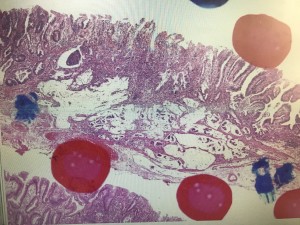

しかし,病理結果としては先進部にmucを有しly1のSM1の診断となりました。

この症例でどうして術前診断を誤ったか,病理上なぜこのような形態を呈するかと白熱した議論が繰り広げられました。

やはりmucがSM浸潤した場合は病変は柔らかいためあまり粘膜下腫瘍様の形態は呈さず,伸展刺激でも容易に変形するため注意が必要であると感じました。